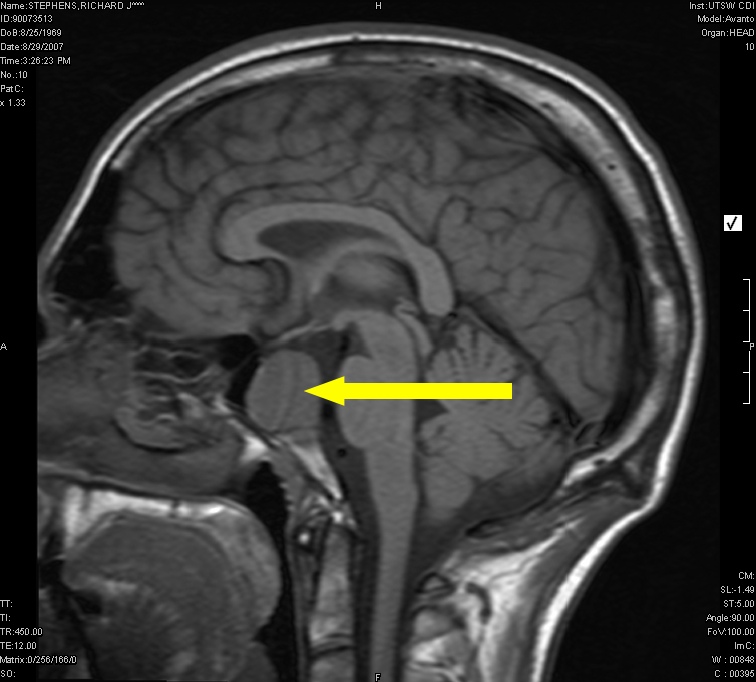

The bean-sized Pituitary gland or "master gland" is extremely important in regulating the function of many other glands and organs of the body . It lies behind and between the eyes at the base of the brain, just beneath the hypothalamus to which it is connected by a thin stalk.

When a functioning tumor is incompletely removed or recurs, further treatment is imperative to try to stop excess hormone secretion. In these cases, the residual tumor is usually small and can often be visualized on an MRI. Gamma Knife radiosrugery is ideally suited for this type of situation